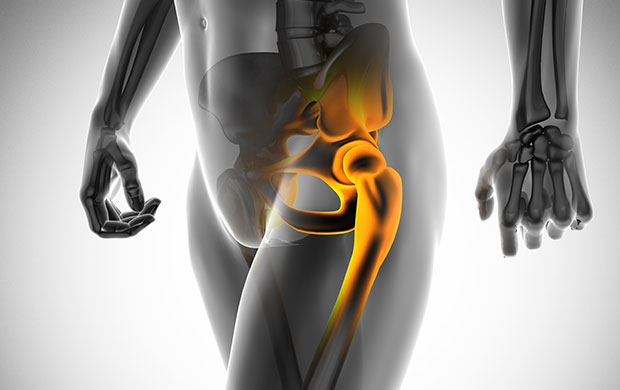

고관절이란?

고관절 통증 증상(엉덩관절)은 오른쪽과 왼쪽의 골반과 넙다리뼈가 연결된 관절의 통증을 일컫습니다. 고관절은 상체의 하중을 분산시키는 역할을 하며, 일어서거나 앉거나 일상생활에서 자주 쓰이는 관절이며 부담도 잘 받게 됩니다. 모양도 크기도 탁구공만 합니다. 일상적으로 걸을 때 고관절에 체중의 3~4.5배의 무게가 실리게 됩니다. 계단을 오를 때는 대퇴골두에 전해지는 무게는 몸무게의 8배, 달리는 경우 10배에 가까운 하중을 견뎌내애 한다고 합니다. 탁구공 크기만 한 대퇴골두가 감당하기에는 너무 무겁기 때문에 고관절이 느끼는 부담도 크고 쉽게 손상될 수 있습니다. 다른 관절과 마찬가지로 감당하기 어려운 충격이나 무게가 가해지면 고관절 통증 증상이 발생하게 되는데요. 퇴행성 고관절염, 대퇴골 골절, 대퇴골두 무혈성 괴사, 선천성 고관절 탈구 등이 대표적인 고관절 통증 질환입니다.